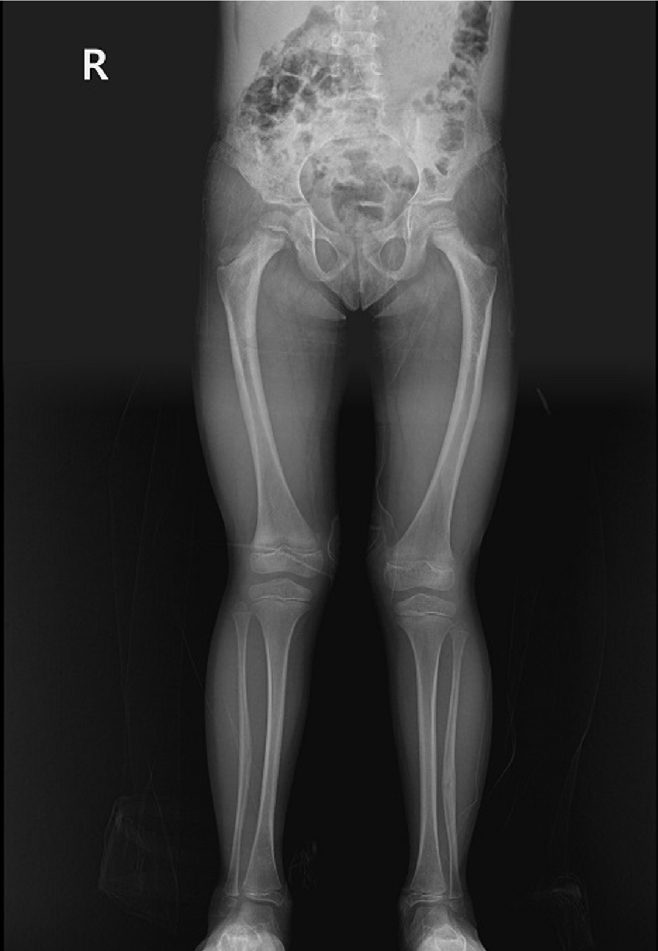

Previous studies have extensively examined the association between femoral insufficiency fractures and prolonged bisphosphonate therapy. However, alternative etiologies remain insufficiently characterized. This study aimed to analyze non-pharmacologic factors associated with femoral insufficiency fractures, with particular emphasis on paradoxical cortical hypertrophy and altered biomechanical load distribution. We reviewed three cases of femoral insufficiency fracture that were surgically treated at our institution between January 2018 and January 2022. None of the patients had a history of bisphosphonate use. Clinical histories—including underlying comorbidities, prior surgical procedures, and radiographic findings—were evaluated. Serial radiographs obtained before and after fracture occurrence were analyzed to characterize fracture morphology and associated cortical changes. Case 1 involved a patient with post-traumatic hip synostosis; case 2 involved a patient with osteogenesis imperfecta; and case 3 involved a patient who had previously undergone intramedullary nailing for an intertrochanteric fracture. Lateral femoral bowing and cortical hypertrophy preceded fracture development in two cases, whereas focal cortical hypertrophy at the distal locking screw site was observed in the third case. No history of bisphosphonate therapy was identified in any patient. Fractures developed at sites characterized by increased cortical remodeling and abnormal load concentration. Femoral insufficiency fractures can occur in the absence of bisphosphonate therapy. Paradoxical cortical hypertrophy and altered biomechanical force distribution appear to be important contributing factors. Level of evidence: IV.